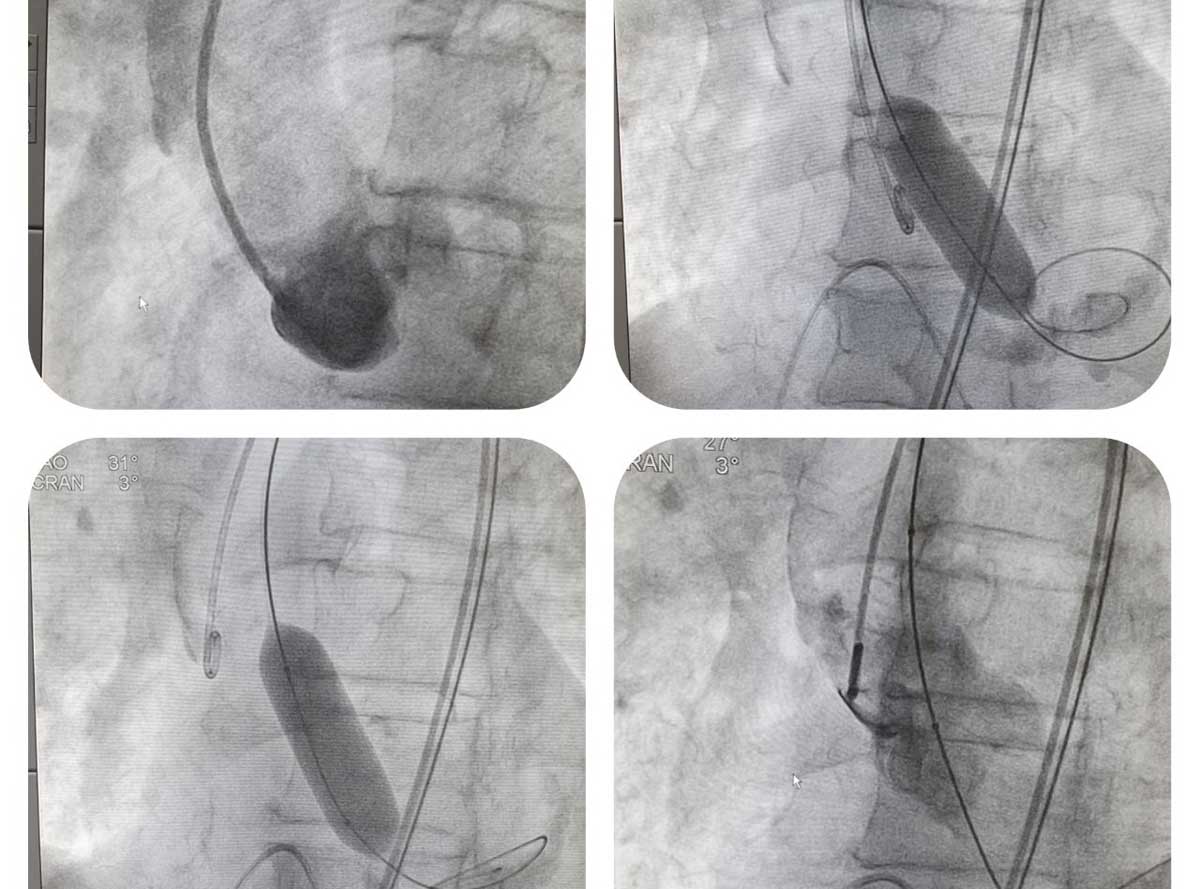

Viterbo – Riceviamo e pubblichiamo – Ieri, presso il laboratorio di Emodinamica, è stata eseguita a Belcolle la prima valvuloplastica aortica per via percutanea.

La procedura, effettuata dal direttore dell’unità operativa di Cardiologia, Luigi Sommariva, e dall’intero staff medico, infermieristico e tecnico del laboratorio, è sostanzialmente consistita nella dilatazione con un palloncino, della valvola aortica severamente malata e ristretta.

“L’intervento – spiega Luigi Sommariva – è avvenuto su un paziente di 80 anni con una serie di comorbidità che, di fatto, ne condizionavano la scelta chirurgica. È l’ennesimo tassello dell’offerta terapeutica in cardiologia interventistica anche per il trattamento di patologie tempo dipendenti, consentendo nel breve periodo l’erogazione della terapia anche in condizioni cliniche di emergenza.

Da qualche anno, in ambito interventistico cardiologico, si è affermata la tecnica del trattamento, per via percutanea, della patologia più frequente della valvola aortica, definita stenosi aortica.

“La dilatazione della valvola, come quella praticata oggi – conclude Sommariva -, consente al paziente di guadagnare tempo prezioso per la definizione del progetto terapeutico ulteriore, laddove si rendesse indicato. L’utilizzo routinario della valvuloplastica, a breve, consentirà di trattare anche quelle condizioni di emergenza che lo richiederanno”.